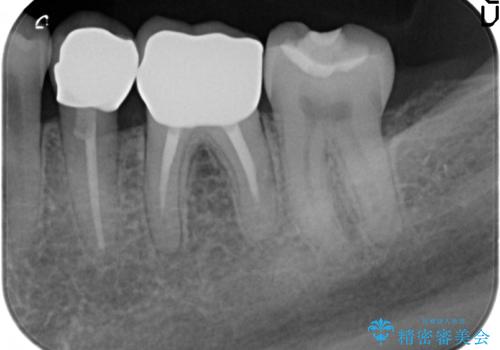

- 20年前に治療した銀歯が壊れ、審美的な修復を希望され来院されました。

銀歯・虫歯を除去し、ジルコニアを咬合再構成を行います。

- 66万円(仮歯・ジルコニアクラウン×6)費用は治療当時の料金となります